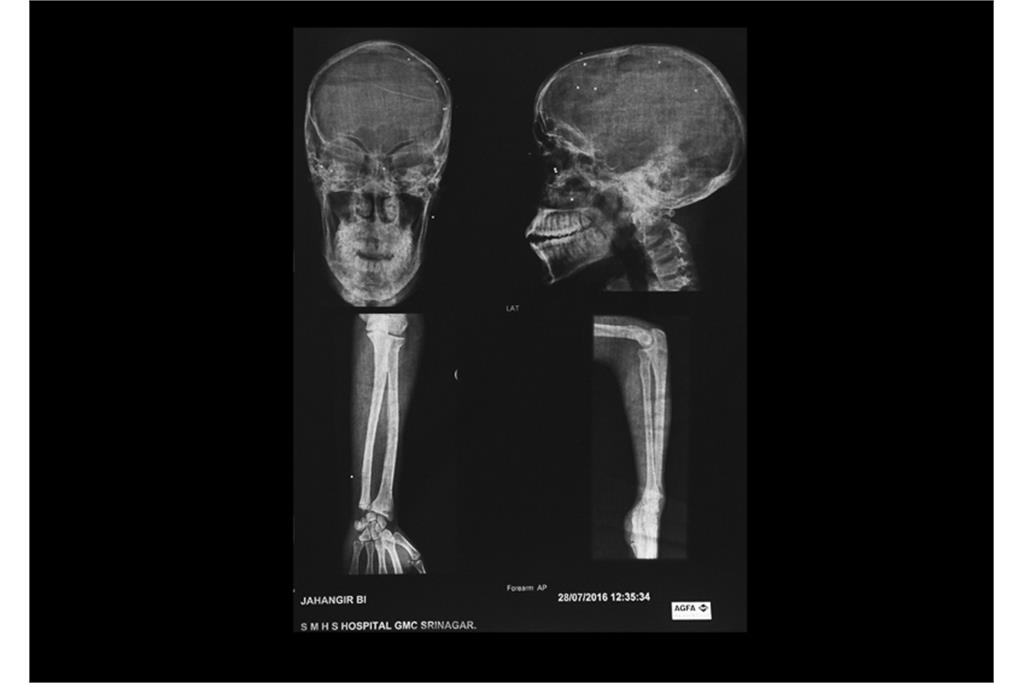

«دره‌ سایه‌ها» مجموعه‌ای از عکس‌ها و اسناد پزشکی در زمینه نقض سیستماتیک حقوق مردمان کشمیر و اعمال شدید‌ترین خشونت‌های دولتی در سرکوب آنها است و نشان دهنده سایه‌ سیاهی که بر دره‌ کشمیر افتاده است و مردمانی که از درون شکسته‌اند. هم‌نشینی بیرون(عکس‌های عادی) و درون (عکس‌های اشعه ایکس)‌ از افراد، تلنگر این فاجعه بر بیننده را دوچندان می‌کند.گویی درد پنهان و آشکار آن‌ها در تاریکی فرو می‌رود و از آن‌ها جز سایه‌ درد و نقطه‌های روشن ترکش‌های داخل بدنشان در عکس‌های اشعه ایکس چیزی باقی نمی‌ماند.